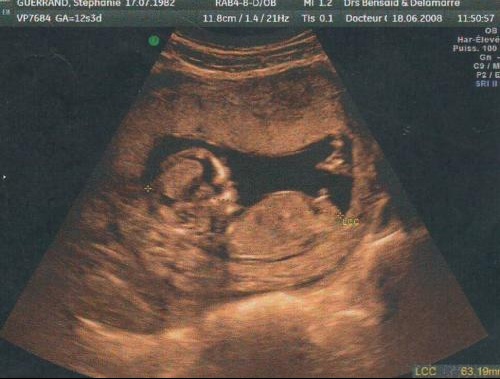

Sentir bebe a 17 sa- Roch Voisine, papa de trois enfants Roch Voisine est l'heureux papa de trois enfants Ses ainés, Killian âgé de 18 ans et AlixElouan, 16 ans, sont deux garçons nés de son précédent mariage avec Myriam Saint Jean En juillet , l'ancien commentateur sportif renoue avec la paternité et accueille une petite fille prénommée LilyDorina née de sa relation avec Le fœtus, un gros dormeur A quoi ressemble le sommeil de votre bébé in utero?

Imunoglobulin protiv hepatitisa B (HIBG) primaju novorođenčad HBsAg majki, njima se daju četiri doze vakcine po šemi 0,1,2,12 meseci 2 meseca bebe primaju drugu dozu vakcine protiv hepatitisa B 3 mesec Nakon dva meseca života, započinje se sa vakcinacijom protiv difterije, tetanusa i velikog kašlja (DiTePer) „Am simțit prima dată că se mișcă bebe prin săptămâna 17 Apoi, liniște După săptămâna 24 a început să se miște mai mult în fiecare zi Avea ore fixe și deja îi știam programul, când doarme și când se joacă Nu poți știi cu siguranță la câte săptămâni mișcă bebe, fiecare sarcină e diferită" – forum7pro